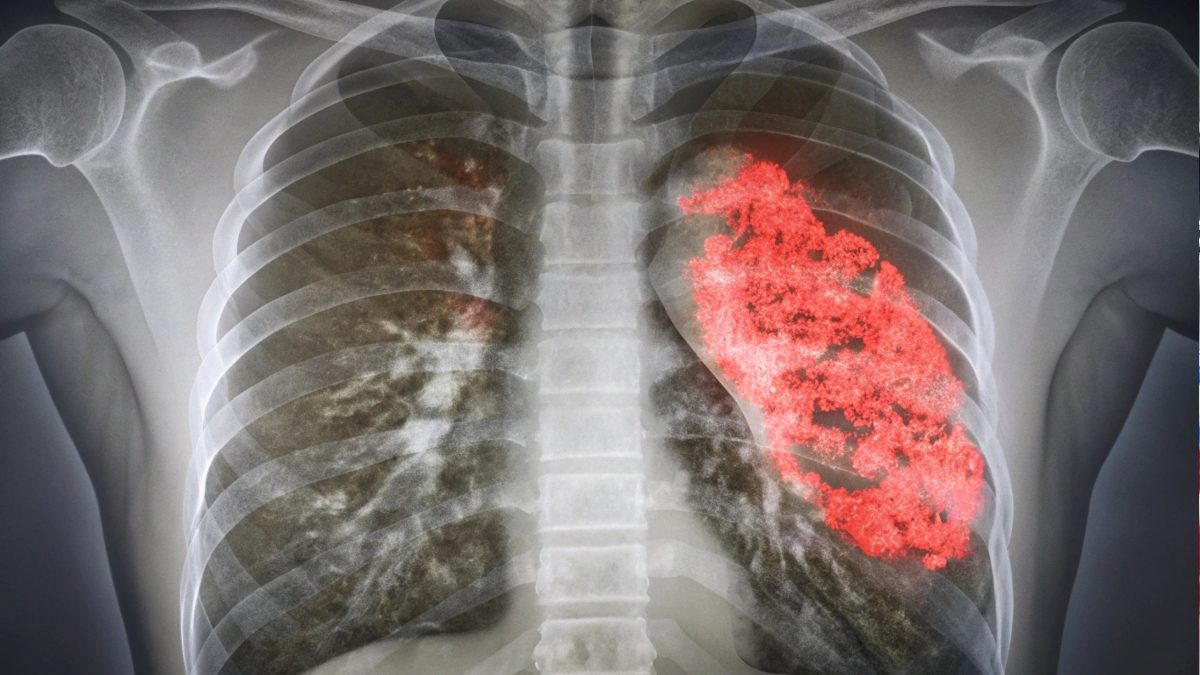

Pneumonia este o infecție a plămânilor cauzată de virusuri, bacterii sau fungi, care reduce cantitatea de oxigen ce ajunge la celulele organismului.

De asemenea, radiografia toracică rămâne cea mai sigură metodă de confirmare, însă trebuie interpretată cu mare precauție, alături de examenul clinic.

Copiii se mișcă adesea în timpul efectuării radiografiei, iar imaginea poate conține artefacte – pete false care pot fi confundate cu semne de pneumonie.

„Radiografia trebuie analizată întotdeauna în contextul clinic. O imagine neclară sau o poziție greșită poate duce la o diagnosticare greșită”, avertizează medicul.

Totodată, opacifierea vizibilă pe radiografie – așa-numita „pată” – poate persista până la șase luni după o infecție anterioară.

Astfel, o nouă radiografie făcută peste câteva săptămâni poate fi interpretată greșit ca o „nouă pneumonie”, deși este doar urma celei vechi.